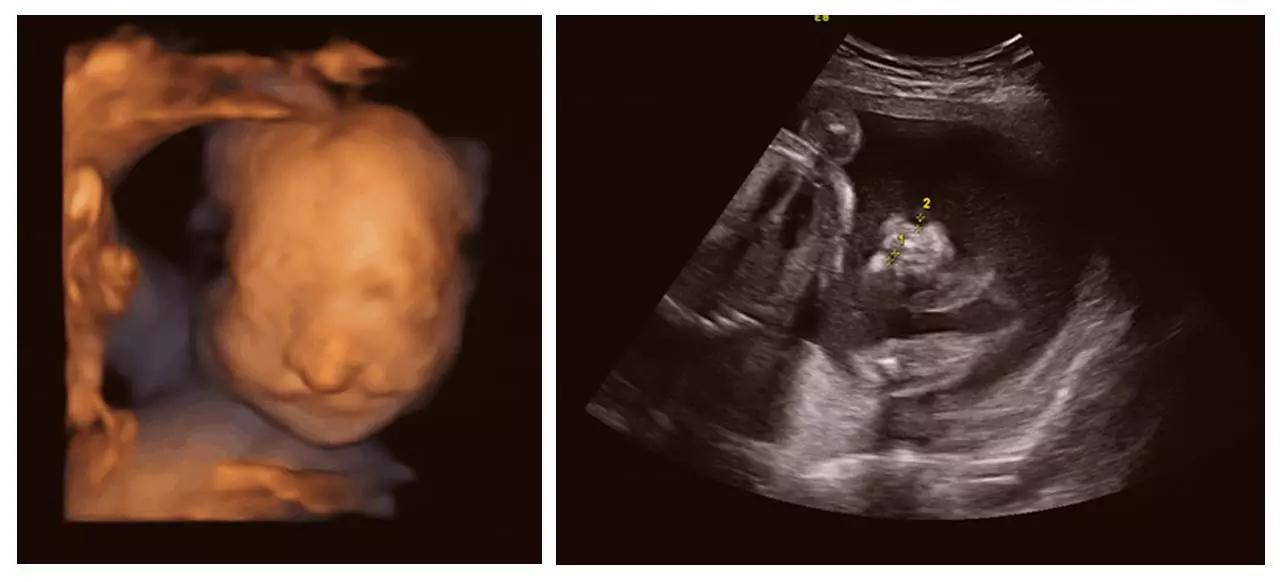

(左心发育不良)

(胸腹腔积液、全身水肿)